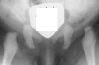

A ten year old female presented with a left hip dislocation. She was born by Cesarean-section because of slow progression of labor. The child was not breech and was noted to have a dislocatable hip at birth. There was a negative family history of DDH. An X-ray prior to application of the brace showed the dislocation of the hip. The patient was first seen at AIDI on 9th day. Abduction of the right hip was 80 degrees but left was only 60 degrees. There was a positive Galeazzi sign with the left hip being shorter than the right. X-rays showed a left hip dislocation and right hip subluxation . A Pavlik harness was applied. After two months, the right hip improved but the left hip was still dislocatable. For this, home traction was started. Even after 2 months, the left hip did not reduce. Therefore, an arthrogram, adductor tenotomy and closed reduction was done at 4 months of age. Single hip spica was applied with the hip in 40 abduction and 100 flexion. Eight weeks later an arthrogram was performed and the cast was reapplied with the hip in 35 degrees abduction and 100 degrees flexion.

Four months later, the spica cast was removed and an Atlanta brace was applied. X-rays showed avascular necrosis at ten months of age . At two years of age, the ossification of the left nucleus was still delayed. The leg lengths were equal and the range of motion of the hip was full.

The progression of the hip is documented by x-rays taken at 1 year of age, 2 years of age, 3 years of

age, 5 years of age, 7 years of age, then at ten years of age, early closure of the lateral portion of proximal growth plate observed. Coxa valga was also observed.